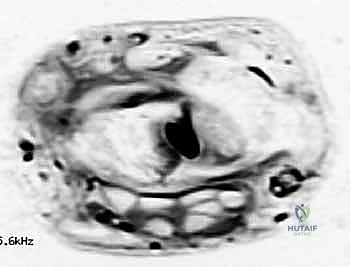

لفهم خطورة وأهمية جراحات أورام اليد، يجب أن نلقي نظرة على التشريح المذهل لهذه المنطقة. يتكون المعصم من ثماني عظام صغيرة (عظام الرسغ) مرتبة في صفين، وترتبط ببعضها بأربطة قوية جداً. يمر عبر هذا المعصم الضيق (نفق الرسغ) أوتار العضلات القابضة بالإضافة إلى العصب المتوسط (Median Nerve).

عندما ينمو ورم (حتى وإن كان حميداً) في هذه المساحة المحدودة، فإنه يبدأ فوراً بالضغط على الهياكل المجاورة. استئصال هذا الورم يتطلب جراحاً متمرساً مثل الأستاذ الدكتور محمد هطيف، الذي يمتلك القدرة على:

الخطوة 3: الاستئصال الميكروسكوبي العميق

هنا تبرز براعة الجراح. باستخدام أدوات الجراحة الميكروسكوبية وعدسات التكبير (Loupes)، يقوم الدكتور هطيف بـ:

* فصل الورم بحذر شديد عن الأنسجة السليمة المحيطة.

* إبعاد وحماية الأعصاب الدقيقة والأوعية الدموية.

* الخطوة الأهم: تتبع عنق (جذر) الورم حتى منبعه في كبسولة المفصل أو غمد الوتر، واستئصاله مع جزء صغير من الكبسولة لضمان عدم تكرار الورم نهائياً.